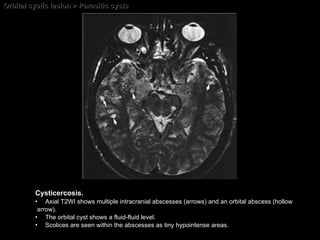

Orbital cystic lesion > Parasitic cysts  Cysticercosis.   Axial T2WI shows multiple intracranial abscesses (arrows) and an orbital abscess (hollow arrow).  The orbital cyst shows a fluid-fluid level.  Scolices are seen within the abscesses as tiny hypointense areas.